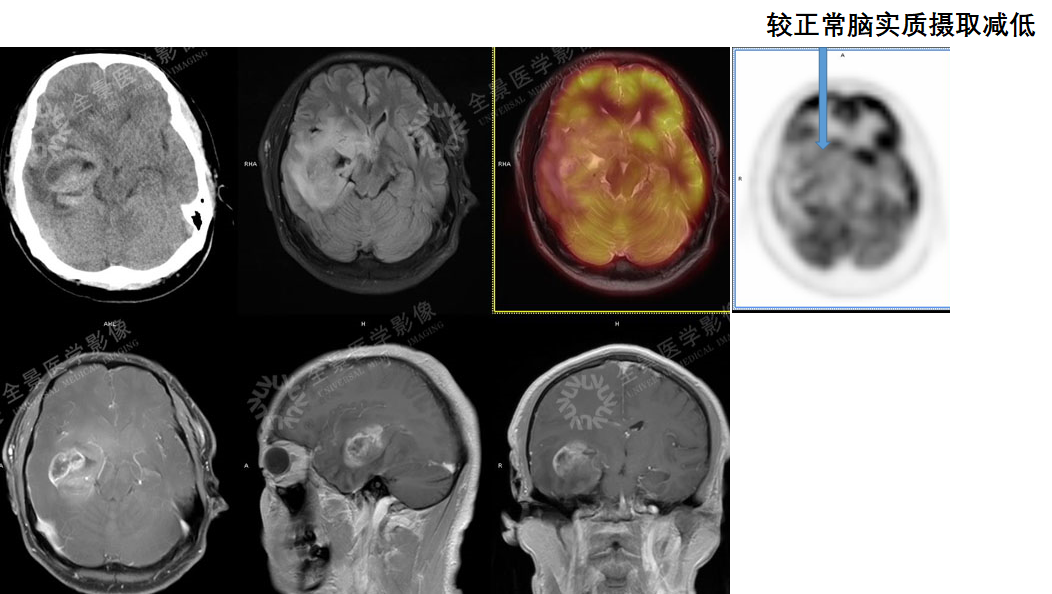

案例1 :胶质瘤与转移瘤鉴别

MR可显示瘤周水肿范围,CT及MR平扫占位效应明显。

胶质瘤与转移瘤鉴别,PET/CT排除转移瘤可能性。MR增强为胶质瘤强化方式。

案例2 :中老年男性,总感觉头晕,外院做头颅增强CT,提示左侧顶叶多发环形强化结节,怀疑脑转移瘤。为进一步明确诊断,行PET/CT-MR异机融合检查。

表现:左侧顶枕叶脑脓肿,邻近脑实质、左侧侧脑室明显受压,右侧脑积水。